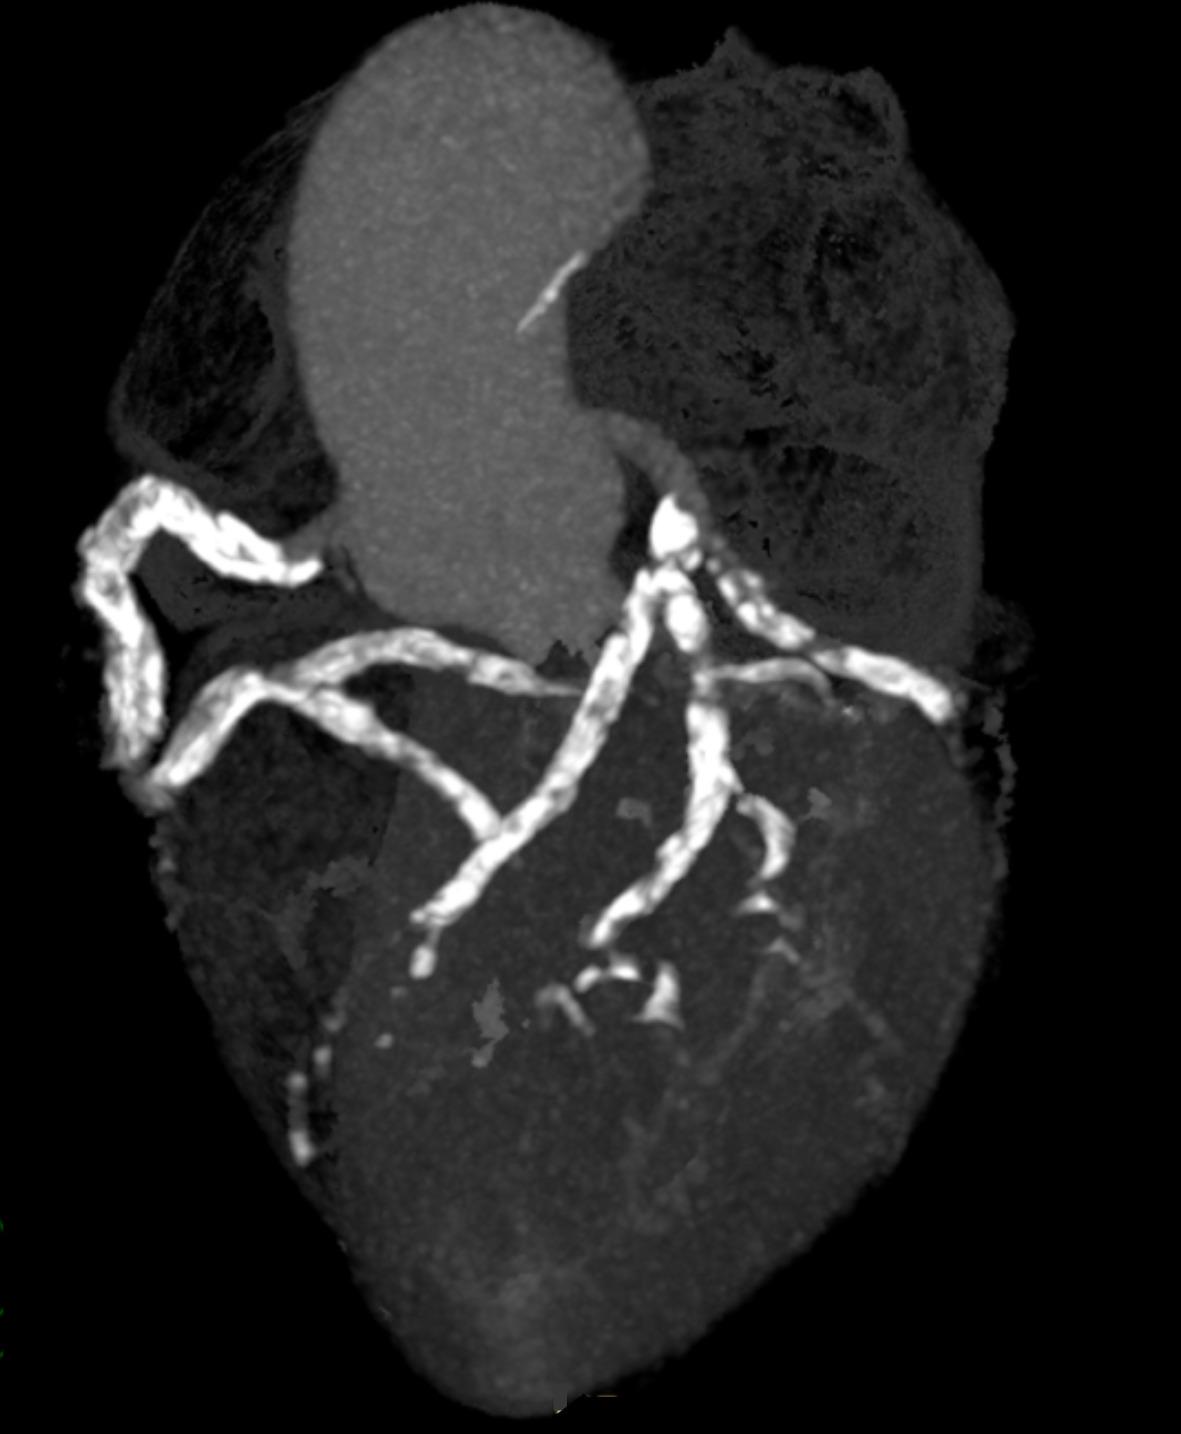

Coronary Artery Disease: Symptoms, Causes & Treatment

Physiology of Coronary Blood Flow | Radiology Key

Plaque characteristics of coronary artery on CCTA. Multiplanar …

Coronary CT Angiography in Coronary Artery Disease: Correlation between …